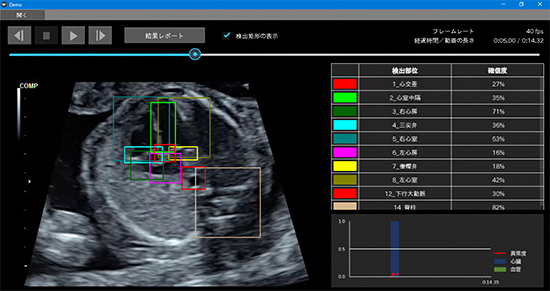

さらに、その技術を用いて、超音波検査の動画上に映るべき胎児心臓と周辺臓器の各部位が実際に映っているかを「確信度(AI自身が予測に対して、どの程度確信を持っているかを示す値)」として高速で算出し、検査画面上にリアルタイムで表示する胎児心臓超音波スクリーニングシステムを構築しました(図2、特許出願中)

図2 今回開発した、胎児心臓超音波スクリーニング異常検知システム

超音波プローブを走査して得られる動画に対して、胎児の心臓と周辺臓器の各部位が実際に映っていたかを「確信度」として高速で算出し、操作画面上にリアルタイムで表示する。左画面の走査断面動画上には実際に検出された部位の位置・範囲を色つきの境界線で囲み、さらに、右上表には算出された各部位の確信度を提示する。また、右下グラフにはその確信度を用いて算出された心臓の構造と血管についての異常度の推移を示す。